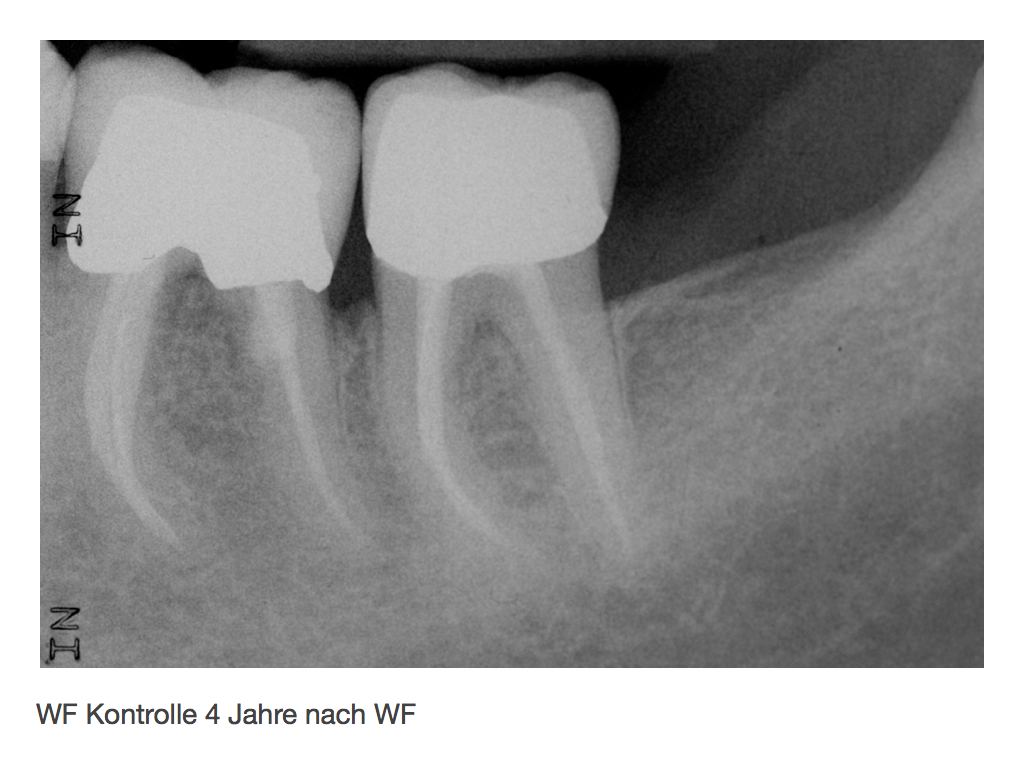

DMAWFR.014 Veröffentlicht 27. Februar 2012 am 1024 × 768 in Die Mutter aller WF – Revisionen – Recall nach 5,5 Jahren